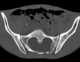

Anterior vertebral scalloping